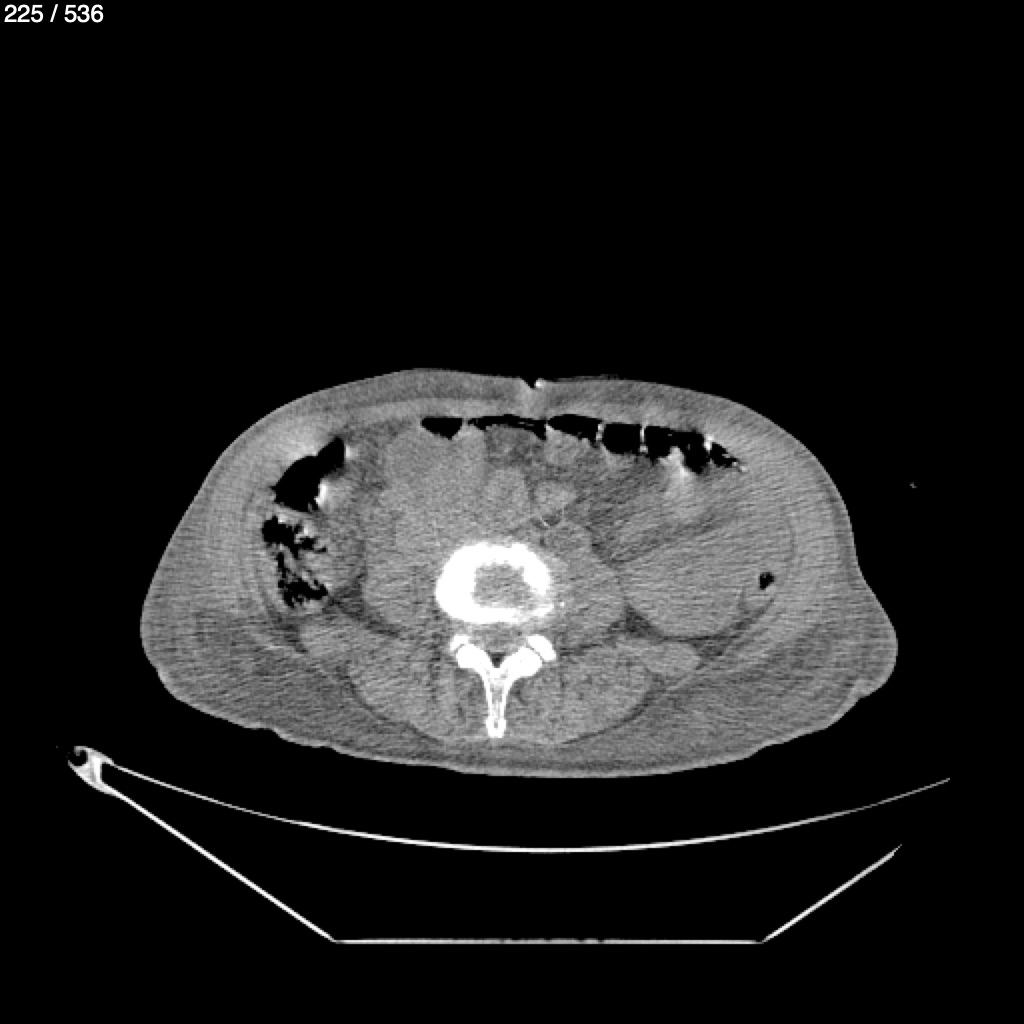

Angel Villalobos Palomeque 73 A - T.C Abdomen Simple